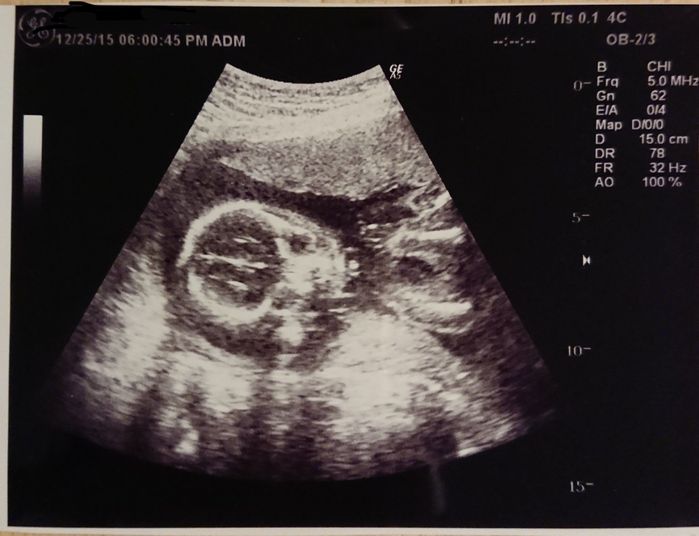

妊娠5週目 胎嚢を確認!

妊娠検査薬で陽性反応が出てから1週間後、産婦人科を受診し、初めてのエコーで胎嚢を確認しました。この時すでにつわりが始まっていたので常にムカムカしている状態です。